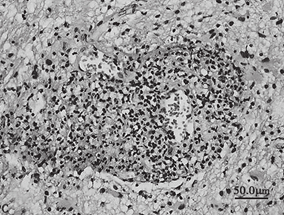

1小时条评论【病例资料】 患者,女性,32岁,医师。因左侧肢体麻木5个月,右侧肢体无力12天,于2005年6月3日收入北京医院神经外科。 现病史:患者于5个月前(2005年1月17日)无明显诱因出现左侧肢体麻木,无力弱、头痛、发热,在当地医院行头颅CT检查未见明显异常,予灯盏花素...